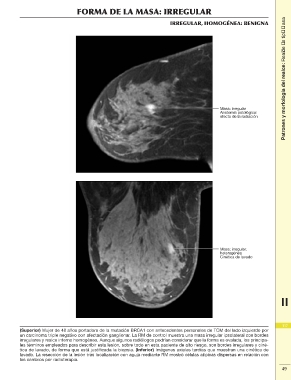

FORMA DE LA MASA: IRREGULAR Patrones y morfología del realce: Realce de tipo masa

IRREGULAR, HOMOGÉNEA: BENIGNA

(Superior) Mujer de 48 años portadora de la mutación BRCA1 con antecedentes personales de TCM del lado izquierdo por 117

un carcinoma triple negativo con afectación ganglionar. La RM de control muestra una masa irregular ipsolateral con bordes

irregulares y realce interno homogéneo. Aunque algunos radiólogos podrían considerar que la forma es ovalada, los principa- 2

les términos empleados para describir esta lesión, sobre todo en esta paciente de alto riesgo, son bordes irregulares y ciné-

tica de lavado, de forma que está justificada la biopsia. (Inferior) Imágenes axiales tardías que muestran una cinética de 49

lavado. La resección de la lesión tras localización con aguja mediante RM mostró células atípicas dispersas en relación con

los cambios por radioterapia.